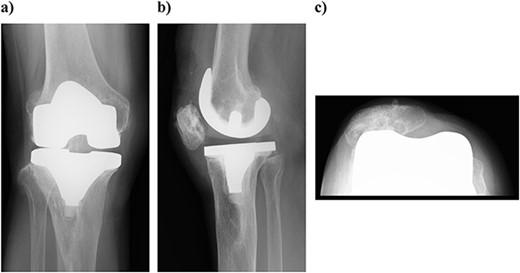

Plain radiography immediately after the surgery: (a) front and (b) lateral side. A slight dilation of the medial joint space is observed.